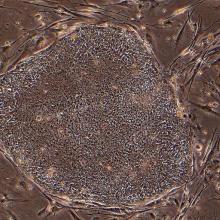

Embryonic stem cell research: an ethical dilemma